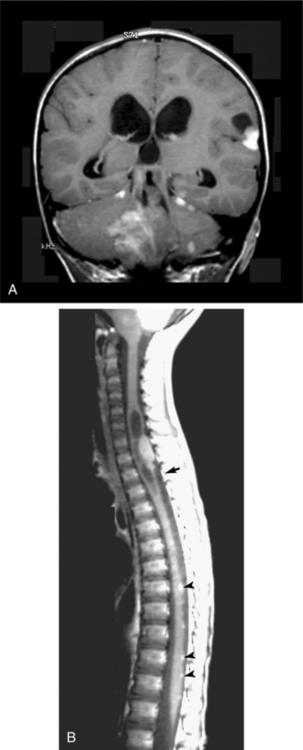

Clinical Manifestations.: Ependymoma is more common in the fourth ventricle and is likely to be detected early because of the signs and symptoms of increased ICP in the posterior fossa (e.g., headache, nausea, vomiting, and papilledema). However, supratentorial ependymomas often grow large before detection. Fig. 30-7 depicts an ependymoma of the fourth ventricle.

Figure 30-7 Ependymoma of the fourth ventricle. Sagittal gadolinium-enhanced T1-weighted (A) and axial T2-weighted (B) magnetic resonance images. A heterogeneously enhanced mass (arrow) fills the lower half of the fourth ventricle and extends through the foramina of Luschka (arrowhead) and Magendie to lie posterior to the medulla oblongata and upper cervical spinal cord, which are compressed from behind. There is obstructive hydrocephalus. (From Grainger and Allison’s diagnostic radiology: a textbook of medical imaging, ed 4, Philadelphia, 2001, Churchill Livingstone.)